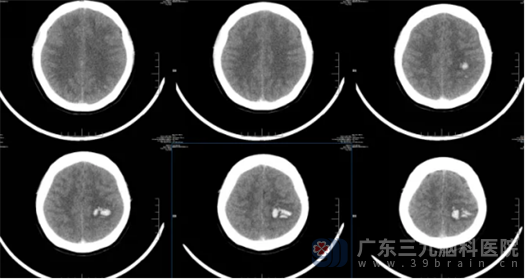

随后,鲁明为患者紧急完善头颅CTV检查,结果提示患者上矢状窦、左侧横窦及乙状窦内血栓形成,相应上矢状窦顶枕部管腔狭窄、余上矢状窦、左侧横窦及乙状窦管腔闭塞;伴左侧额顶叶静脉淤积所致脑出血。经过详细的检查和诊断,最终确诊患者是产后静脉窦血栓。